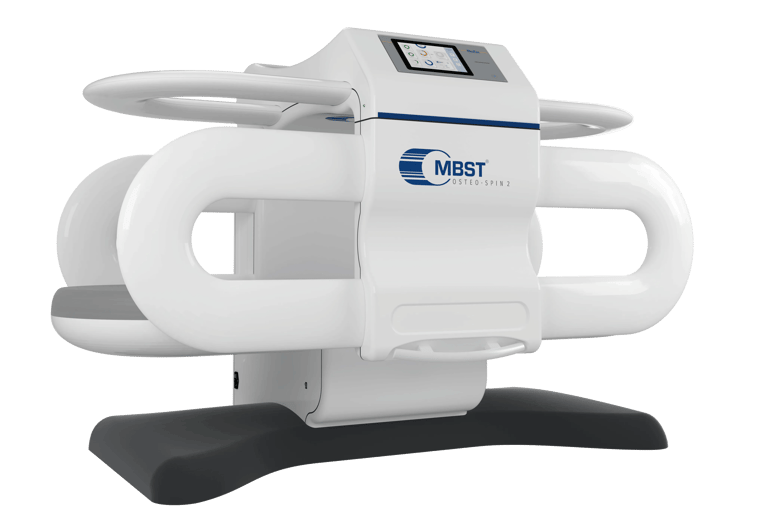

MBST Therapy Advanced Non-Surgical Solution for Joint & Spine Pain

MBST is an innovative German technology that uses therapeutic magnetic resonance to stimulate cell regeneration, repair cartilage, and relieve chronic pain without surgery, injections, or radiation.

Advanced medical technology focused on cellular repair

MBST uses precise magnetic resonance signals to create conditions that support healthy cell activity and natural repair. When cells operate the way they’re meant to, they can better restore balance, regenerate tissue, relieve discomfort, and reduce inflammation.